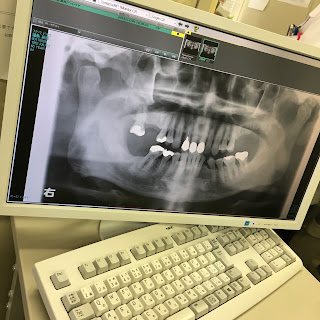

学生時代にADでお世話になった小川宏ショーの同窓会を欠席されて気になっていたが、出演者もスタッフも、名前をフルネームでいつまでも覚えておられた名司会者小川さんの死を悼む。そんな基本を教えてもらったことを思い出しながら、きょうから鶴見大通い。金属アレルギーの原因が歯の補綴成分と特定されたので、つめた9カ所をセラミックに替える大工事に突入。

41年前! 写真左上の5:45入局から後日の報告コーナー担当としてベタづき。左下は小川宏テレソンの最後、各局司会者を集めた深夜番組(25:40終了)で。右はきょう撮った歯全体がわかるパノラマ・レントゲン写真。金属部分は白い9本。